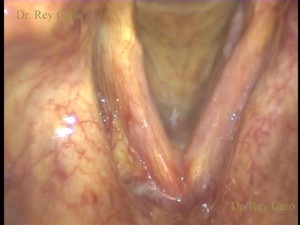

Imagen intraoperatoria con telescopio de 0°. Papilomatosis de cuerda vocal izquierda.

Intraoperative image of left vocal cord papillomatosis